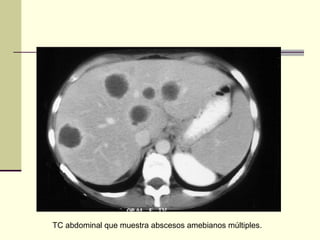

TC abdominal que muestra abscesos amebianos múltiples.

Absceso hepático amebiano Ecografíade un absceso hepático único TAC con absceso hepático único

TC abdominal quemuestra abscesos amebianos múltiples.